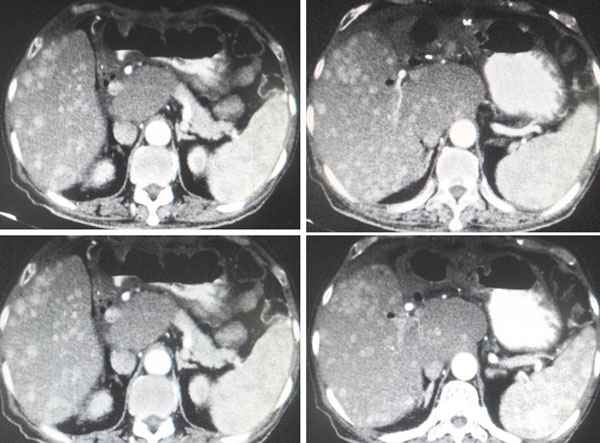

Fast forward to April 2018 – a repeat Triphasic CT scan showed:

- A solitary non-enchancing homogenous isodense liver nodule 3.3 x 3.6 cm. In view of underlying chronic hepatitis carrier, need to exclude atypical hepatocellular carcinoma.

- Associated underlying liver cysts and haemangioma.

A follow up CT in July 2020 showed:

- Increasing size and number of liver lesions in segment 2 and 3.

- Lung nodules with pleural-based lesions suggestive of lung and pleural metastases.

- Prostatomegaly with chronic bladder obstruction.